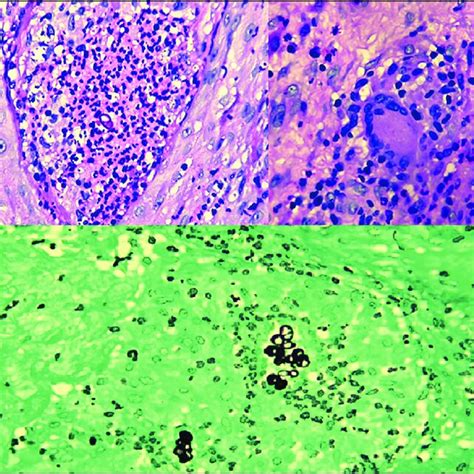

Hallazgos Histopatológicos

El examen microscópico de la biopsia puede revelar:

- Hiperqueratosis ortoqueratósica.

- Espongiosis, que es el edema intercelular en la epidermis.

- Exocitosis, que es la presencia de células inflamatorias en la epidermis.

- Apoptosis ocasional de queratinocitos.

- Infiltrado inflamatorio en la dermis, que puede incluir eosinófilos y neutrófilos.

En algunos casos, se pueden observar características adicionales que sugieren una causa específica, como daño vasculítico o liquenoide.